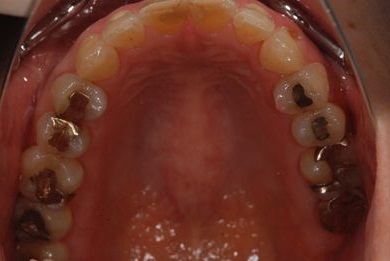

性別/年齢 女性 / 54歳

主訴 抜歯したところのインプラント治療を希望。

治療内容 インプラント1本、メタルボンドセラミック1本

治療部位

7

治療前

• 治療前